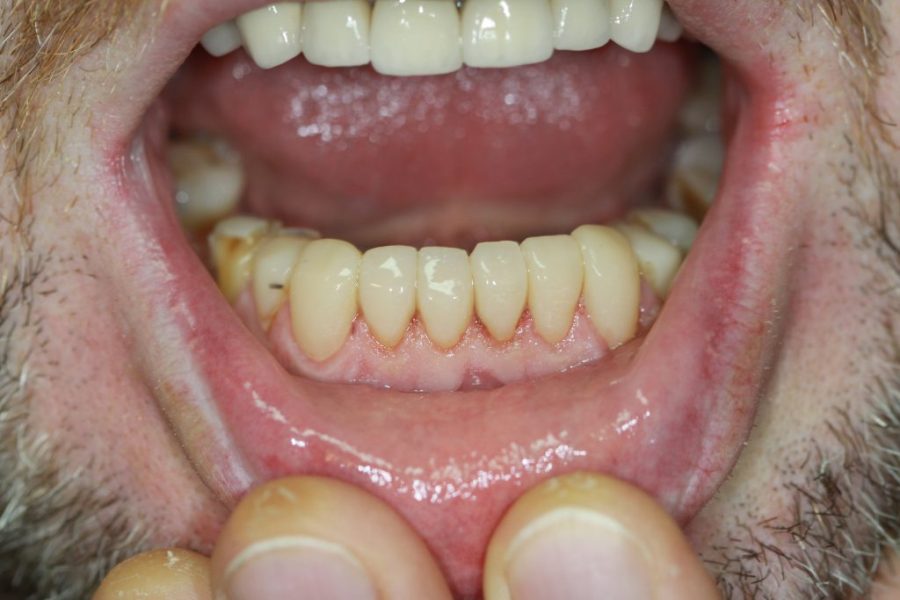

Henry’s Story: A Full Smile Makeover

Henry’s broken teeth were impacting his confidence. With a combination of root canal therapy, laser gum surgery, crowns, and dentures, we restored his smile over four weeks. Now, his family and grandchildren are thrilled with his transformation.